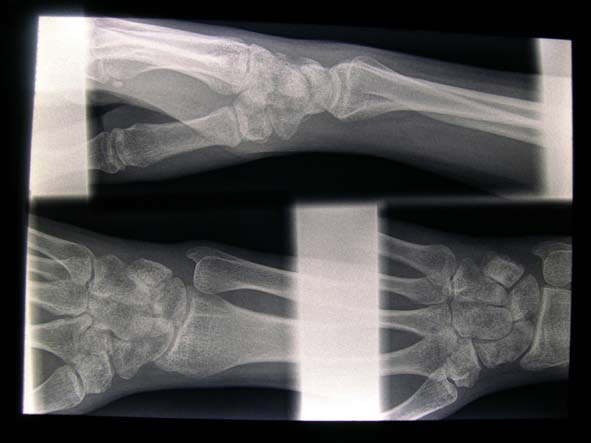

I perceive the feeling of being airborne on a bike and the experience of recovering from injury as complete opposites. It is a move from feeling graceful, strong and able to conquer anything to being clumsy, slow, weak and barely coping with everyday tasks. Once the hospital has immobilised you and the injured area of the body stiffens up then even basic tasks are painfully slow; tying shoe laces, brushing hair, getting dressed. Navigating around public space I am aware of how fragile I am and how vulnerable I am compared to others. I am constantly aware that my body’s function is impaired. In A Leg to stand on Oliver Sacks writes about his experience of breaking his leg and says he felt like an animal with a broken back dragging its hind legs along (1990: 26). I feel disadvantaged in relation to others, upset by the diminished functionality of my body and bored by restrictions on what I can do. Just living basic life, getting up and showering and dressing takes so much more time and I feel how little I am able to achieve. I long for excitement and adrenaline but my body is not capable of doing the things that produce this. The passiveness makes me feel like I am in a room and watching life on a TV set, as if there is a gap between what I see and what is there. It is as if what I see and experience outside of myself is not ‘real’.